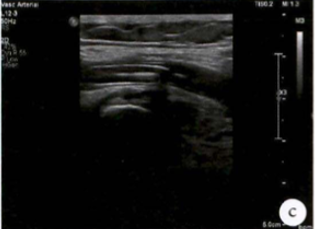

术前检查:右髂动脉血栓

图:术前CT

图:术前超声